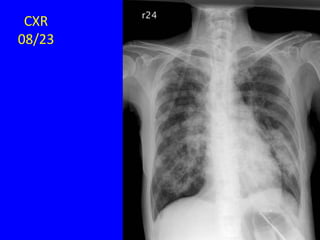

CXR

08/21

08/23

08/28

08/31

HRCT

09/01

09/09

09/15